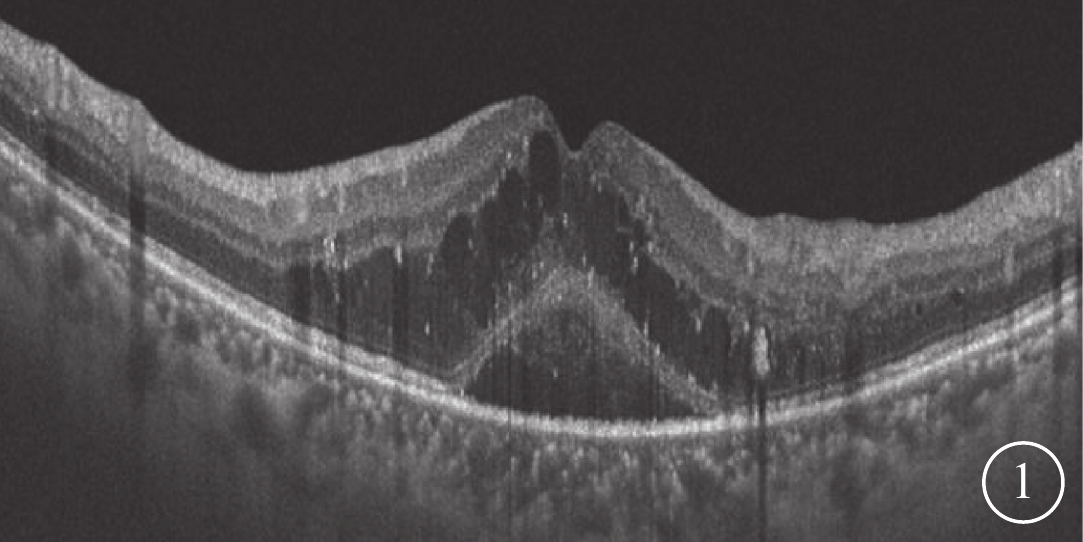

2017年11月至2018年8月于解放軍中部戰區總醫院眼科檢查確診的DME患者19例24只眼納入本研究。其中,男性8例11只眼,女性11例13只眼。年齡42~61歲,平均年齡(52.46±5.52)歲;病程150~735 d,平均病程(323.42±149.67)d。納入標準:(1)眼底檢查確診為有臨床意義DME;(2)患眼3次及以上玻璃體腔注射抗VEGF藥物治療后黃斑CMT>275 μm,且OCT檢查發現黃斑部神經上皮層間或神經上皮層下弱反射暗腔(圖1)。排除標準:(1)既往有玻璃體視網膜手術史;(2)既往有黃斑變性、葡萄膜炎、眼外傷、視網膜脫離、黃斑裂孔、黃斑前膜、高度近視、青光眼、其他視網膜血管性疾病以及重度白內障等眼病史;(3)黃斑部或黃斑旁RPE萎縮、黃斑部或黃斑旁新生血管增生膜形成;(4)合并糖尿病視神經萎縮或新生血管性青光眼;(5)合并有全身其他器官疾病不適宜手術者。